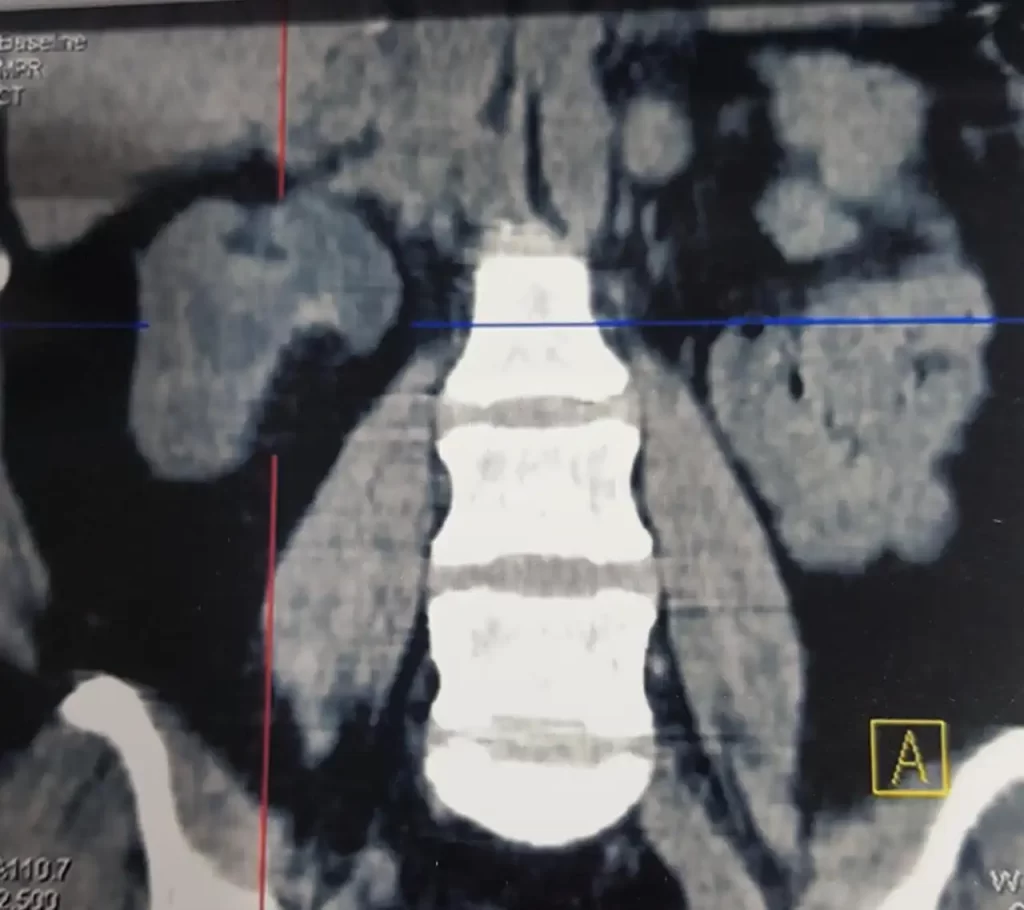

No definite mass on the ct scan as kidney was non functioning